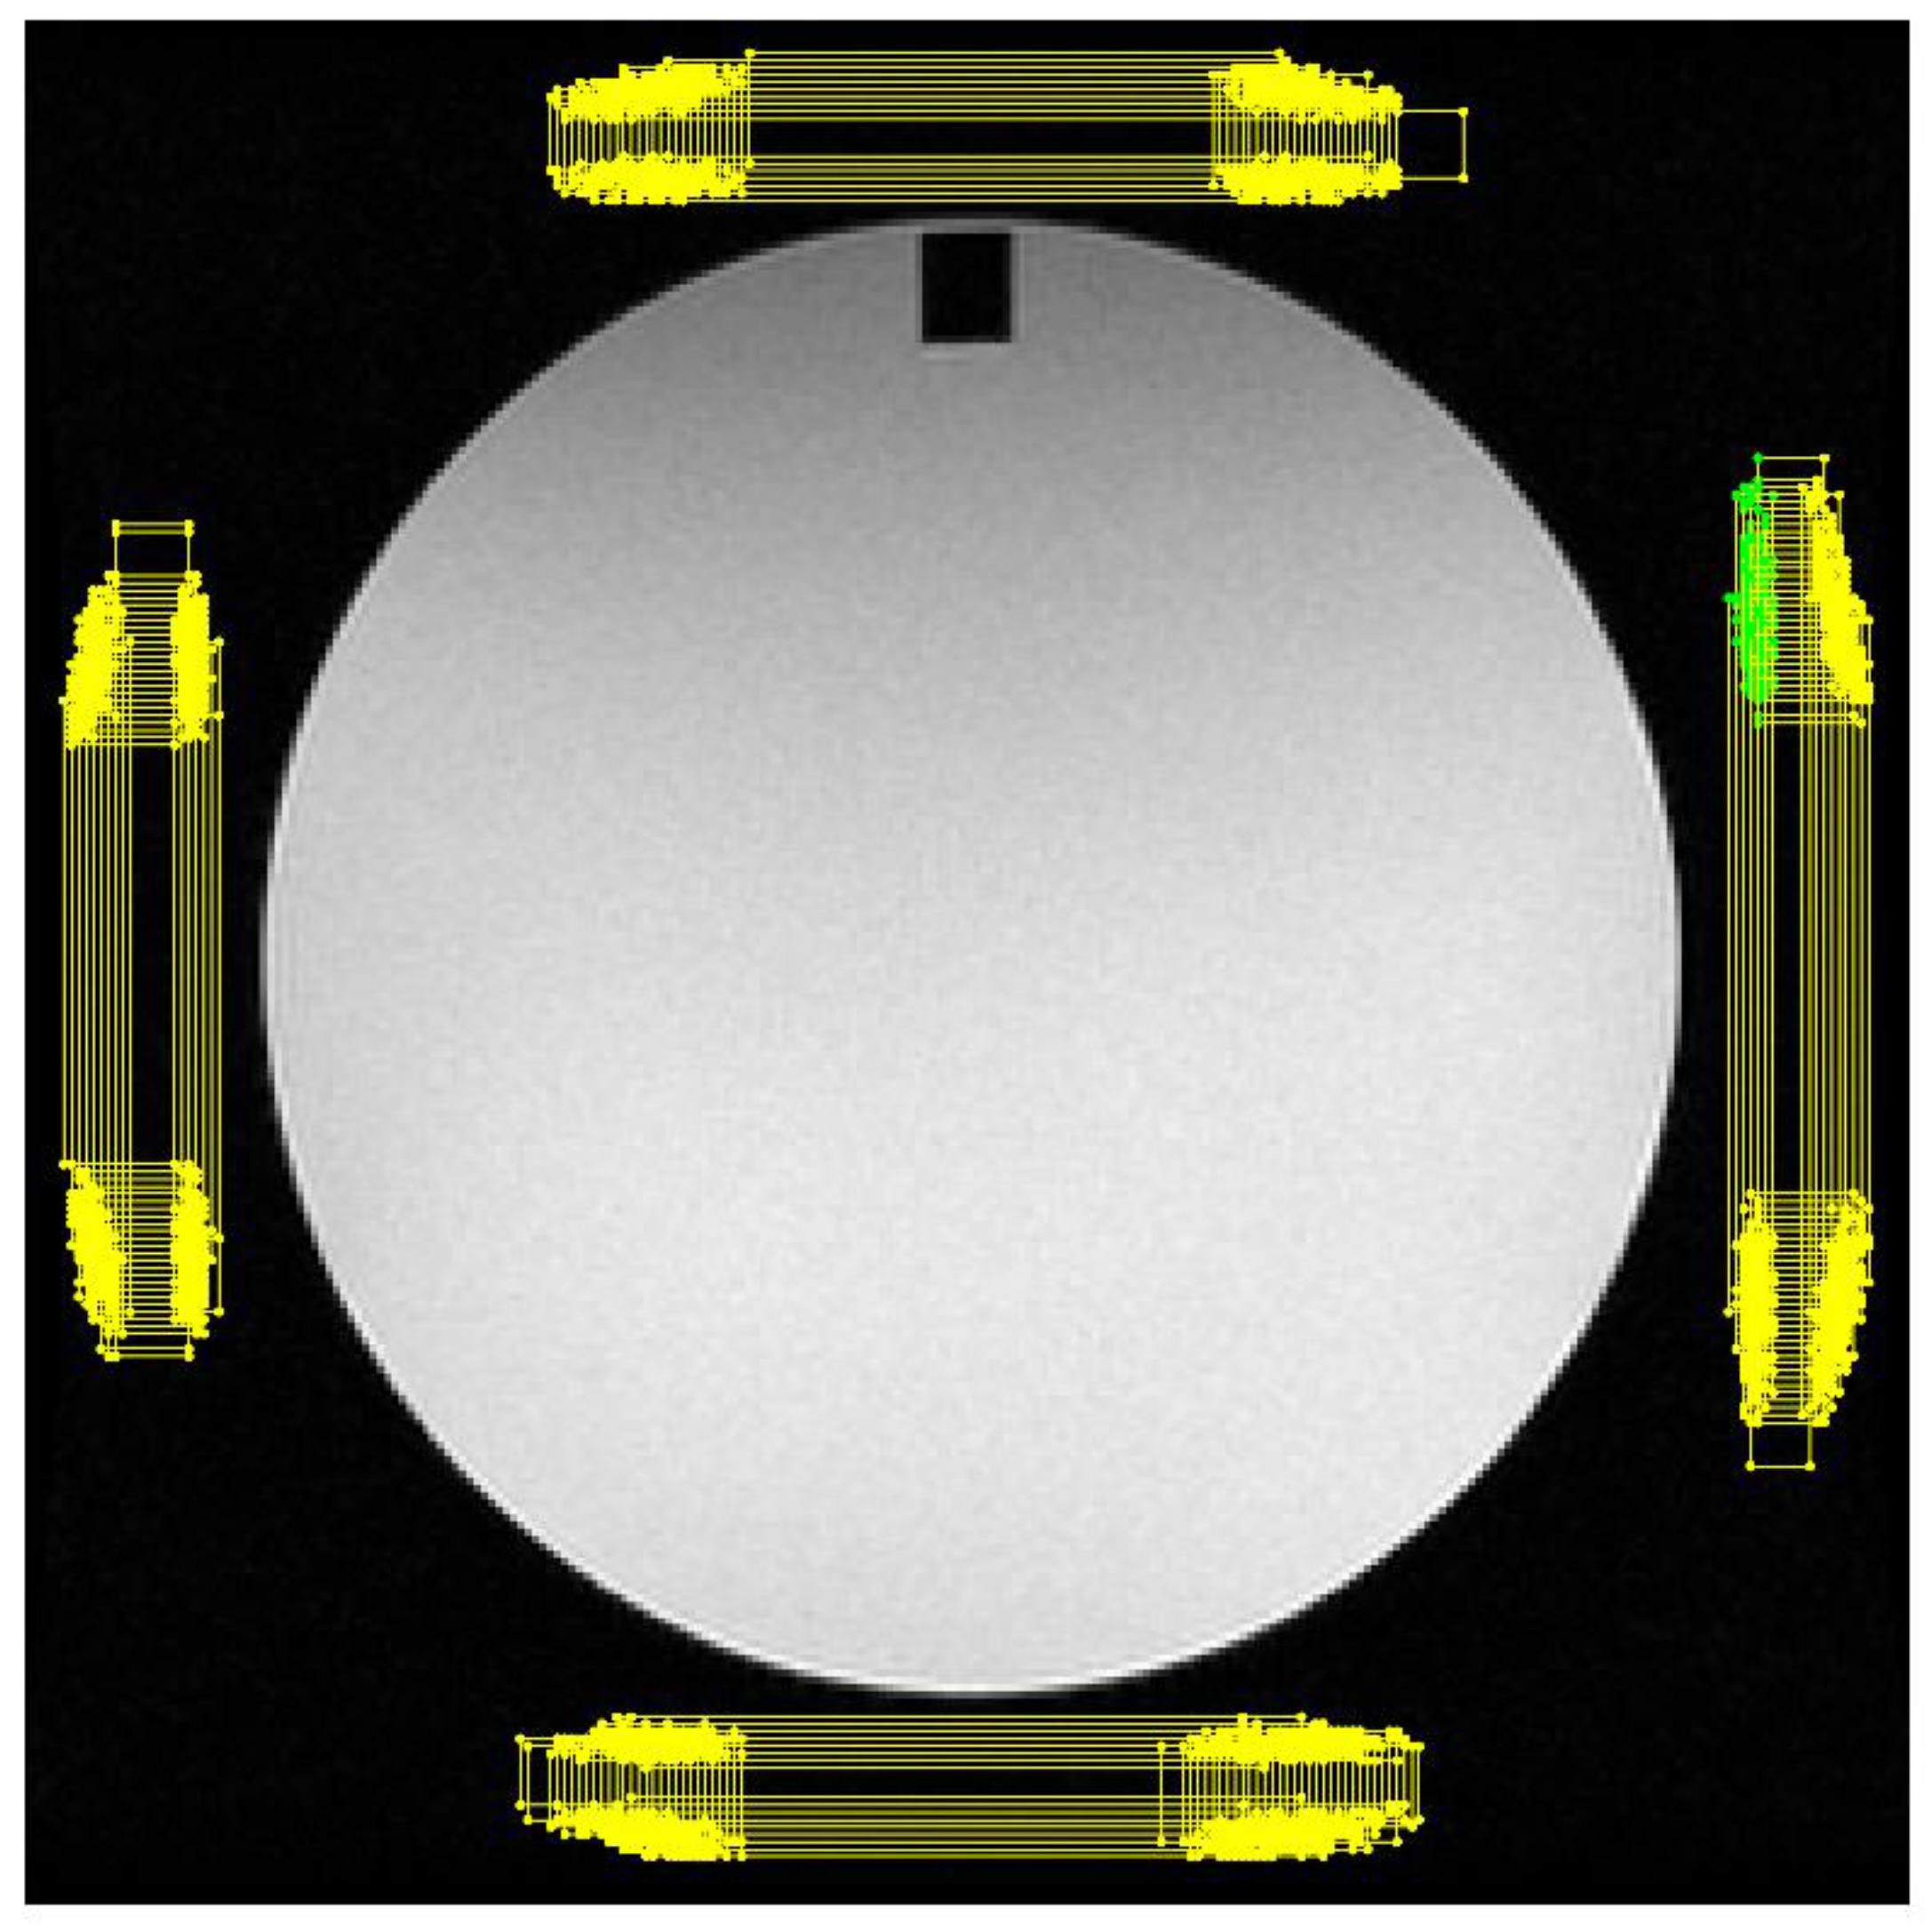

- SNR is calculated by Equation (5), applied to a single image (slice #7), using as numerator the mean intensity values of the main circular ROI () and as denominator the average of the standard deviations of the left and right rectangular ROI , shown in Figure 2 as proposed in the Greek protocol [17]. Therefore, Equation (5) becomes: